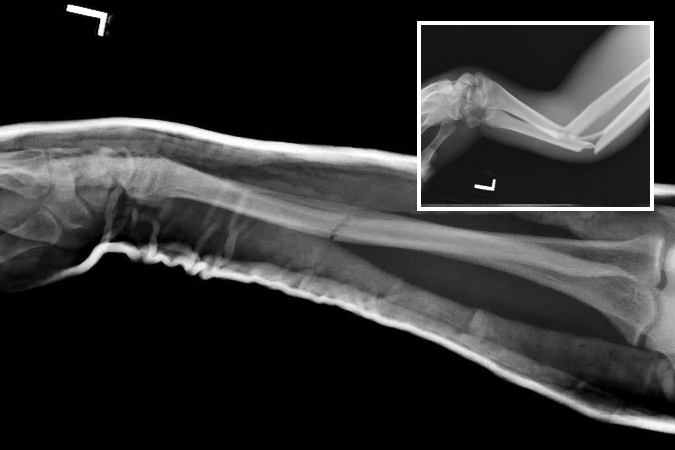

Greenstick fracture

- Pediatric forearm fractures are typically described as either complete or greenstick fractures.4

- Greenstick fractures are incomplete, partial thickness fractures in which only the cortex and periosteum are interrupted on one side of the bone but intact on the other side.4,18

- Greenstick fractures are more common among younger children under the age of 10 years, particularly boys, while completed or short oblique fractures are more common in older children.18,19

- The most common mechanism of injury is a fall on an outstretched hand (FOOSH), but other possible causes include car accidents, bike accidents, sports injuries, and non-accidental trauma.18

Imaging

- Radiology studies - X-ray